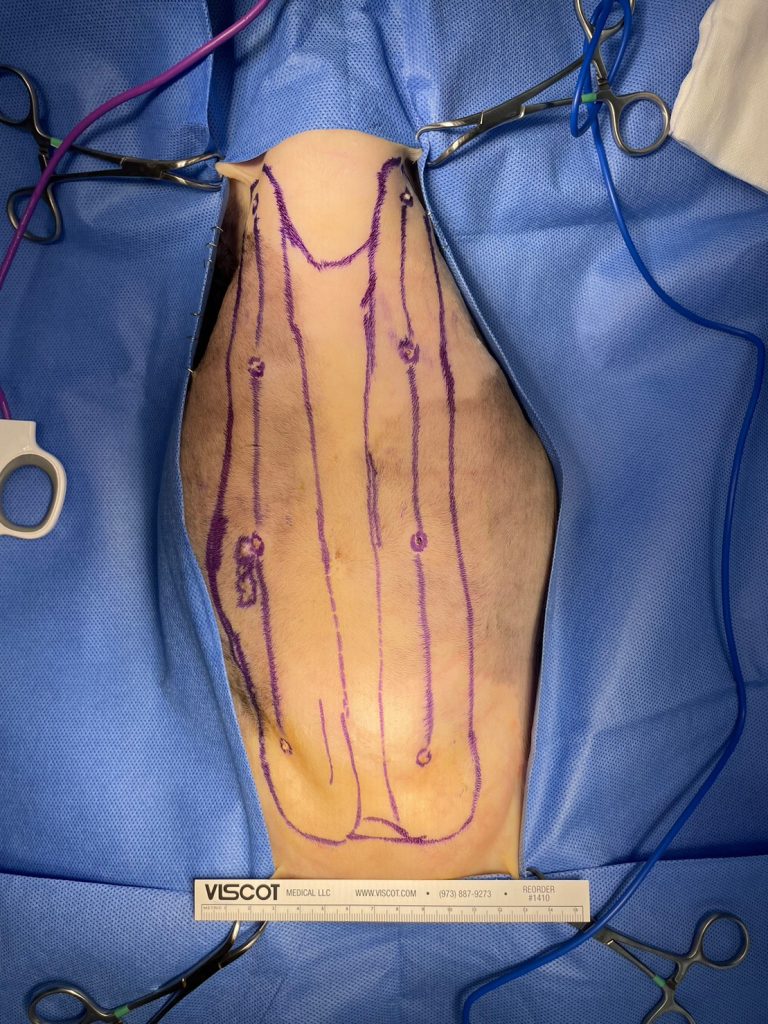

2023年8月8日,手術日:

我們兩位外科醫師在確認Kulo的皮膚張力可以承受後,以極佳的默契順利的完成雙側全乳腺切除,而腫瘤區則多切一層腹壁肌肉。

我們隨即開始手術。